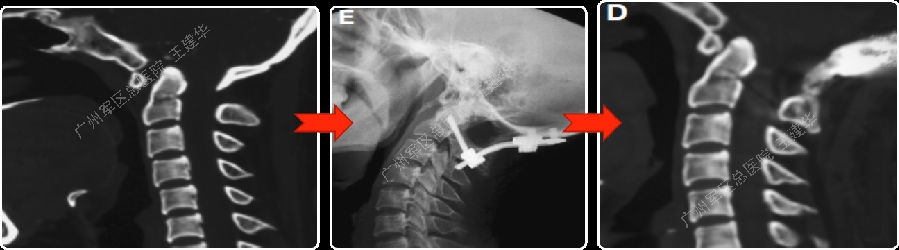

术前术后对比

病例2

手术前后对比

手术后CT显示,陷入枕骨大孔的齿突获得下拉复位

术后MRI发现,患者的颅底凹陷,脊髓空洞和Chiari畸形均获改善